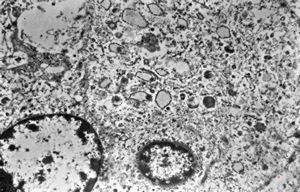

F, 24y. | molluscum contagiosum … virions

F, 24y. | molluscum contagiosum

F, 24y. | molluscum contagiosum